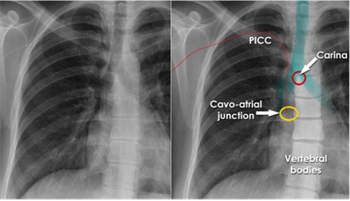

除此之外,因为兼具了动态成像的多功能性和移动机型的优越的灵活性,这个机器展现了造福临床广阔的适用性,例如床旁引导PICC置管、床旁引导输液港植入、床旁引导各类引流插管小手术等等,造福多科室,以往,行这类手术往往是护士依靠自身经验,而现在在动态可视化影像的引导下,这类插管置管手术能进行得更加顺利。不用任何影像引导的话,“盲穿”就全凭技术人员的感觉和经验,此时,移动动态DR给置管的准确性带来了可靠的影像学评估方法。